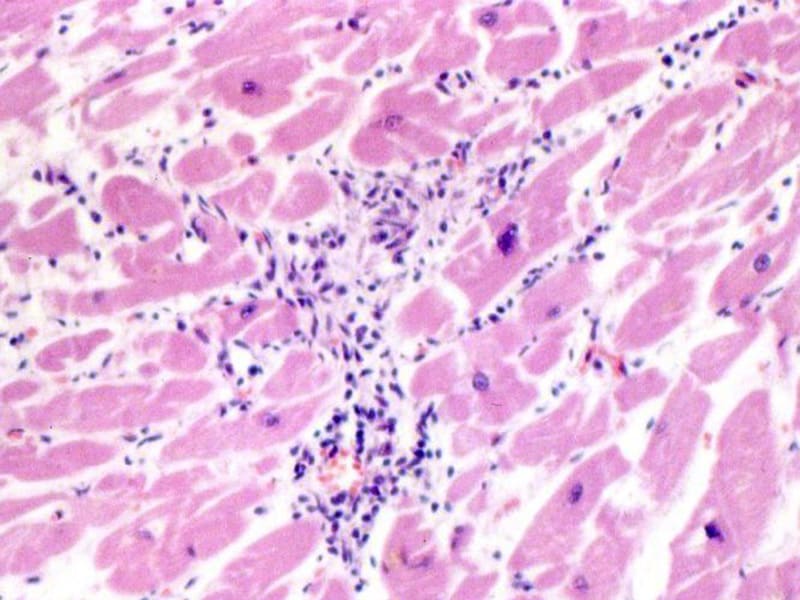

Межуточный миокардит: гистологические исследования